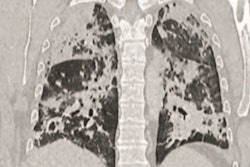

The team found that, overall, ground-glass opacities and consolidations were the main CT signs of COVID-19 disease. But there were some differences in CT findings by age, which included the following:

- Patients between the ages of 45 and 59 and those 60 and older had more bilateral lung, lung lobe, and lung field involvement, and greater lesion numbers than patients younger than 18.

- Ground-glass opacity along with interlobular septa thickening or a crazy-paving pattern, consolidation, and the air bronchogram sign were more common in patients between the ages of 45 and 59 and those 60 and older than in those younger than 18 or between 18 and 44.

"In this study, the key finding is that the middle-aged and elderly patients have the most severe representation of parenchymal findings, and follow with the morphological appearance that seems to be particularly limited in the youngest group, which provides certain support for clinical individualized treatment of patients of different ages," the team wrote.